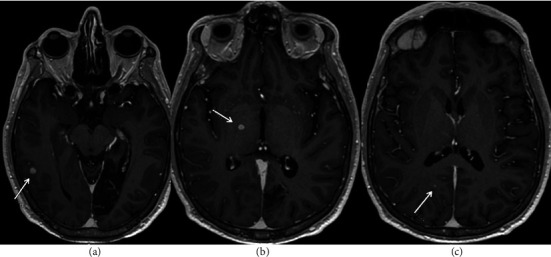

组织胞浆菌病是一种由真菌荚膜组织胞浆菌引起的真菌感染,很少出现中枢神经系统(CNS)表现,包括脑膜炎、脑炎、局灶性脑或脊髓病变以及中风综合征。由于患者之间的差异,中枢神经系统组织浆菌病是一种难以进行临床诊断的疾病,而没有高灵敏度的诊断测试则进一步阻碍了诊断。在这里,我们提出一个独特的案例,46岁的男性免疫功能低下,由于1型糖尿病和弥散性组织胞浆菌病作为脊髓病的急性表现。患者在就诊前几天左腿无力,神经学检查显示有急性胸椎脊髓病的迹象,特别是与布朗-萨默综合征有关。核磁共振成像显示胸脊髓强化病灶,同时伴有多发脑强化病灶,双侧肾上腺肿块和无数肺结节。活检结果显示酵母形式与组织浆菌种类一致。

Histoplasmosis is a fungal infection caused by the fungus Histoplasma capsulatum that can rarely present with central nervous system (CNS) manifestations that include meningitis, encephalitis, focal brain or spinal cord lesions, and stroke syndromes. Because of this variation from patient to patient, CNS histoplasmosis is a difficult clinical diagnosis to make, which can be further hindered by no highly sensitive diagnostic testing available. Here, we present a unique case of a 46-year-old male immunocompromised due to type 1 diabetes mellitus with disseminated histoplasmosis as an acute presentation of myelopathy. Patient had left leg weakness for a few days prior to presentation and a neurological exam remarkable for signs of acute thoracic myelopathy, specifically concerning for Brown-Séquard syndrome. MRI imaging demonstrated an enhancing thoracic spinal cord lesion along with multiple cerebral enhancing lesions, bilateral adrenal masses, and innumerable pulmonary nodules. Biopsy results demonstrated yeast forms consistent with Histoplasma species.